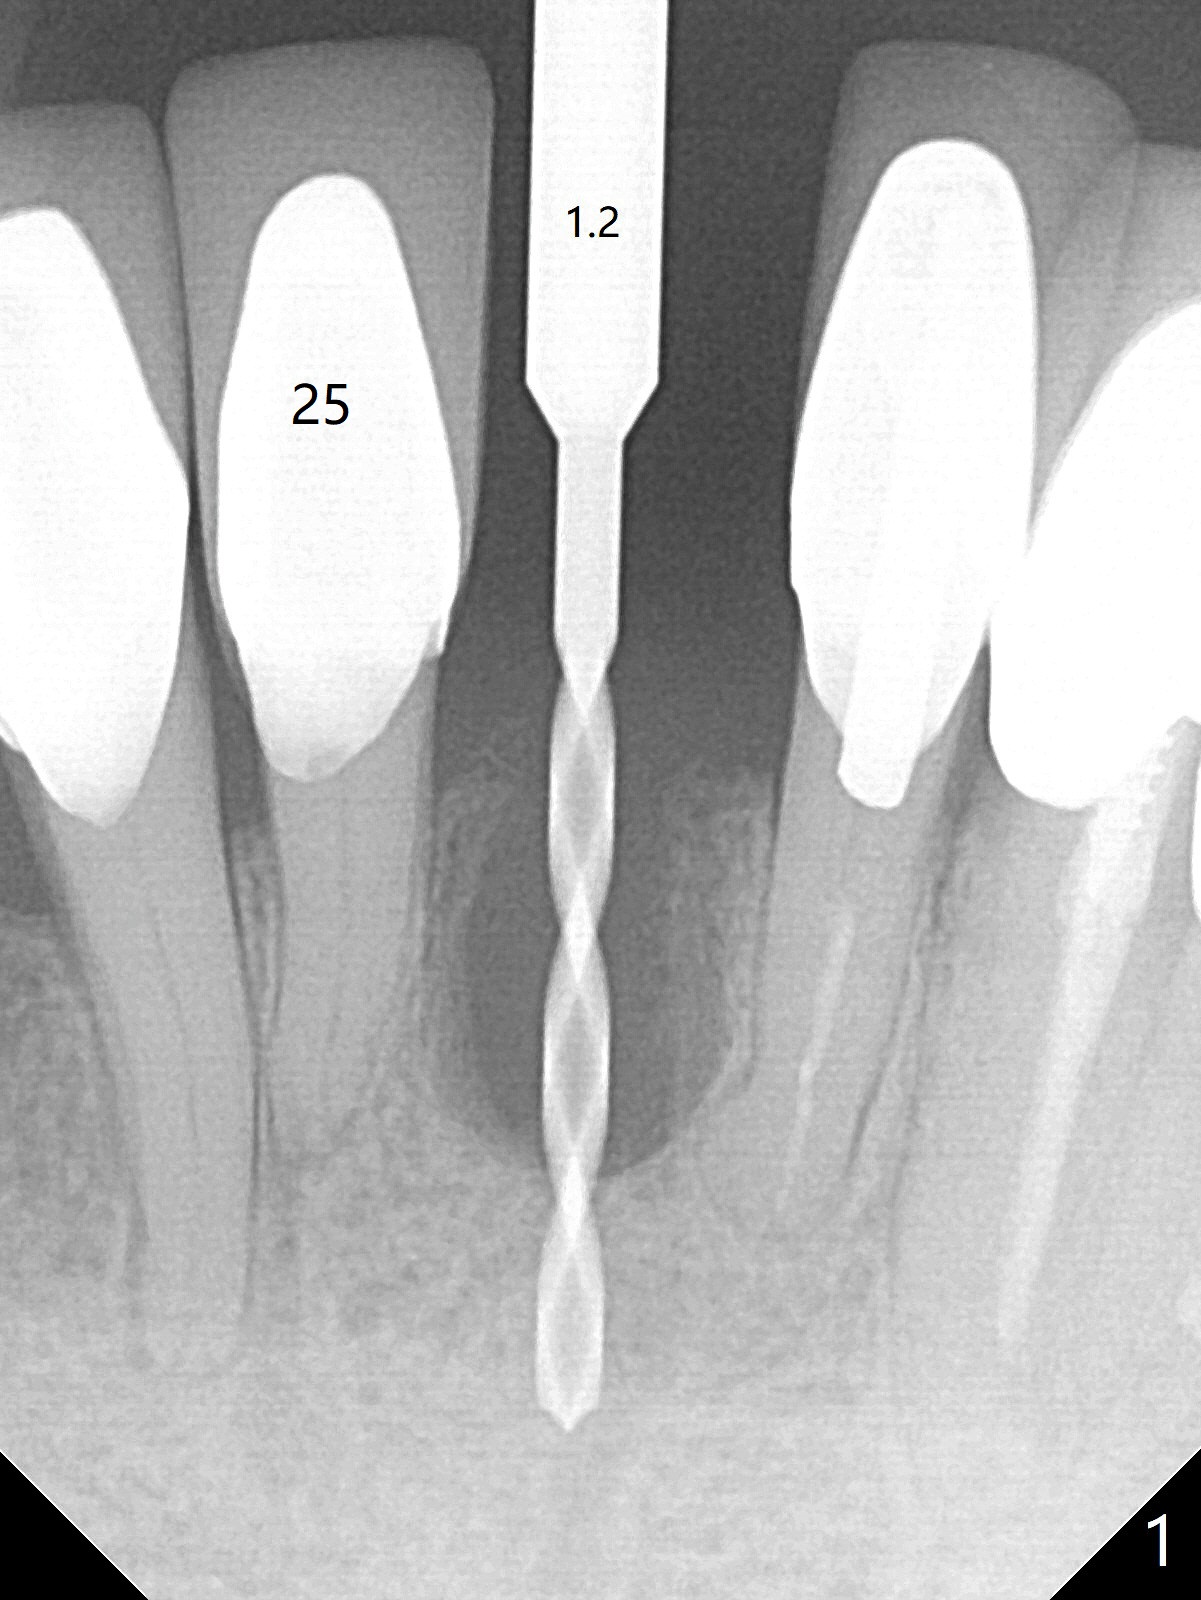

After extraction of the tooth #24 with vertical root fracture (loss of buccolingual plates), osteotomy is initiated with 1.2 mm drill free hand; the trajectory seems satisfactory (Fig.1). With sequential osteotomy, a 2.5x14(2) mm 1-piece implant has difficulty being placed deep (Fig.2), apparently associated with dense bone. Allograft is placed not only mesiodistal (Fig.2,4 *), but also buccolingual (Fig.3,5,6 *) to cover the exposed implant threads. In fact inability to place the implant deep is due to the apex of the implant (Fig.5,6 x) touching the lingual (L) cortical plate. If surgical guide were used, the implant placement difficulty would not occur. The surgery would be shorter and easier. The seemingly easiest implant placement should be assisted with a guide! In addition, preop CT would dictate implant placement in the middle of the socket buccolingual. The lingual (Fig.7 *) and buccal (Fig.8 <) gingiva remains bulky, although asymptomatic, 8 days postop.